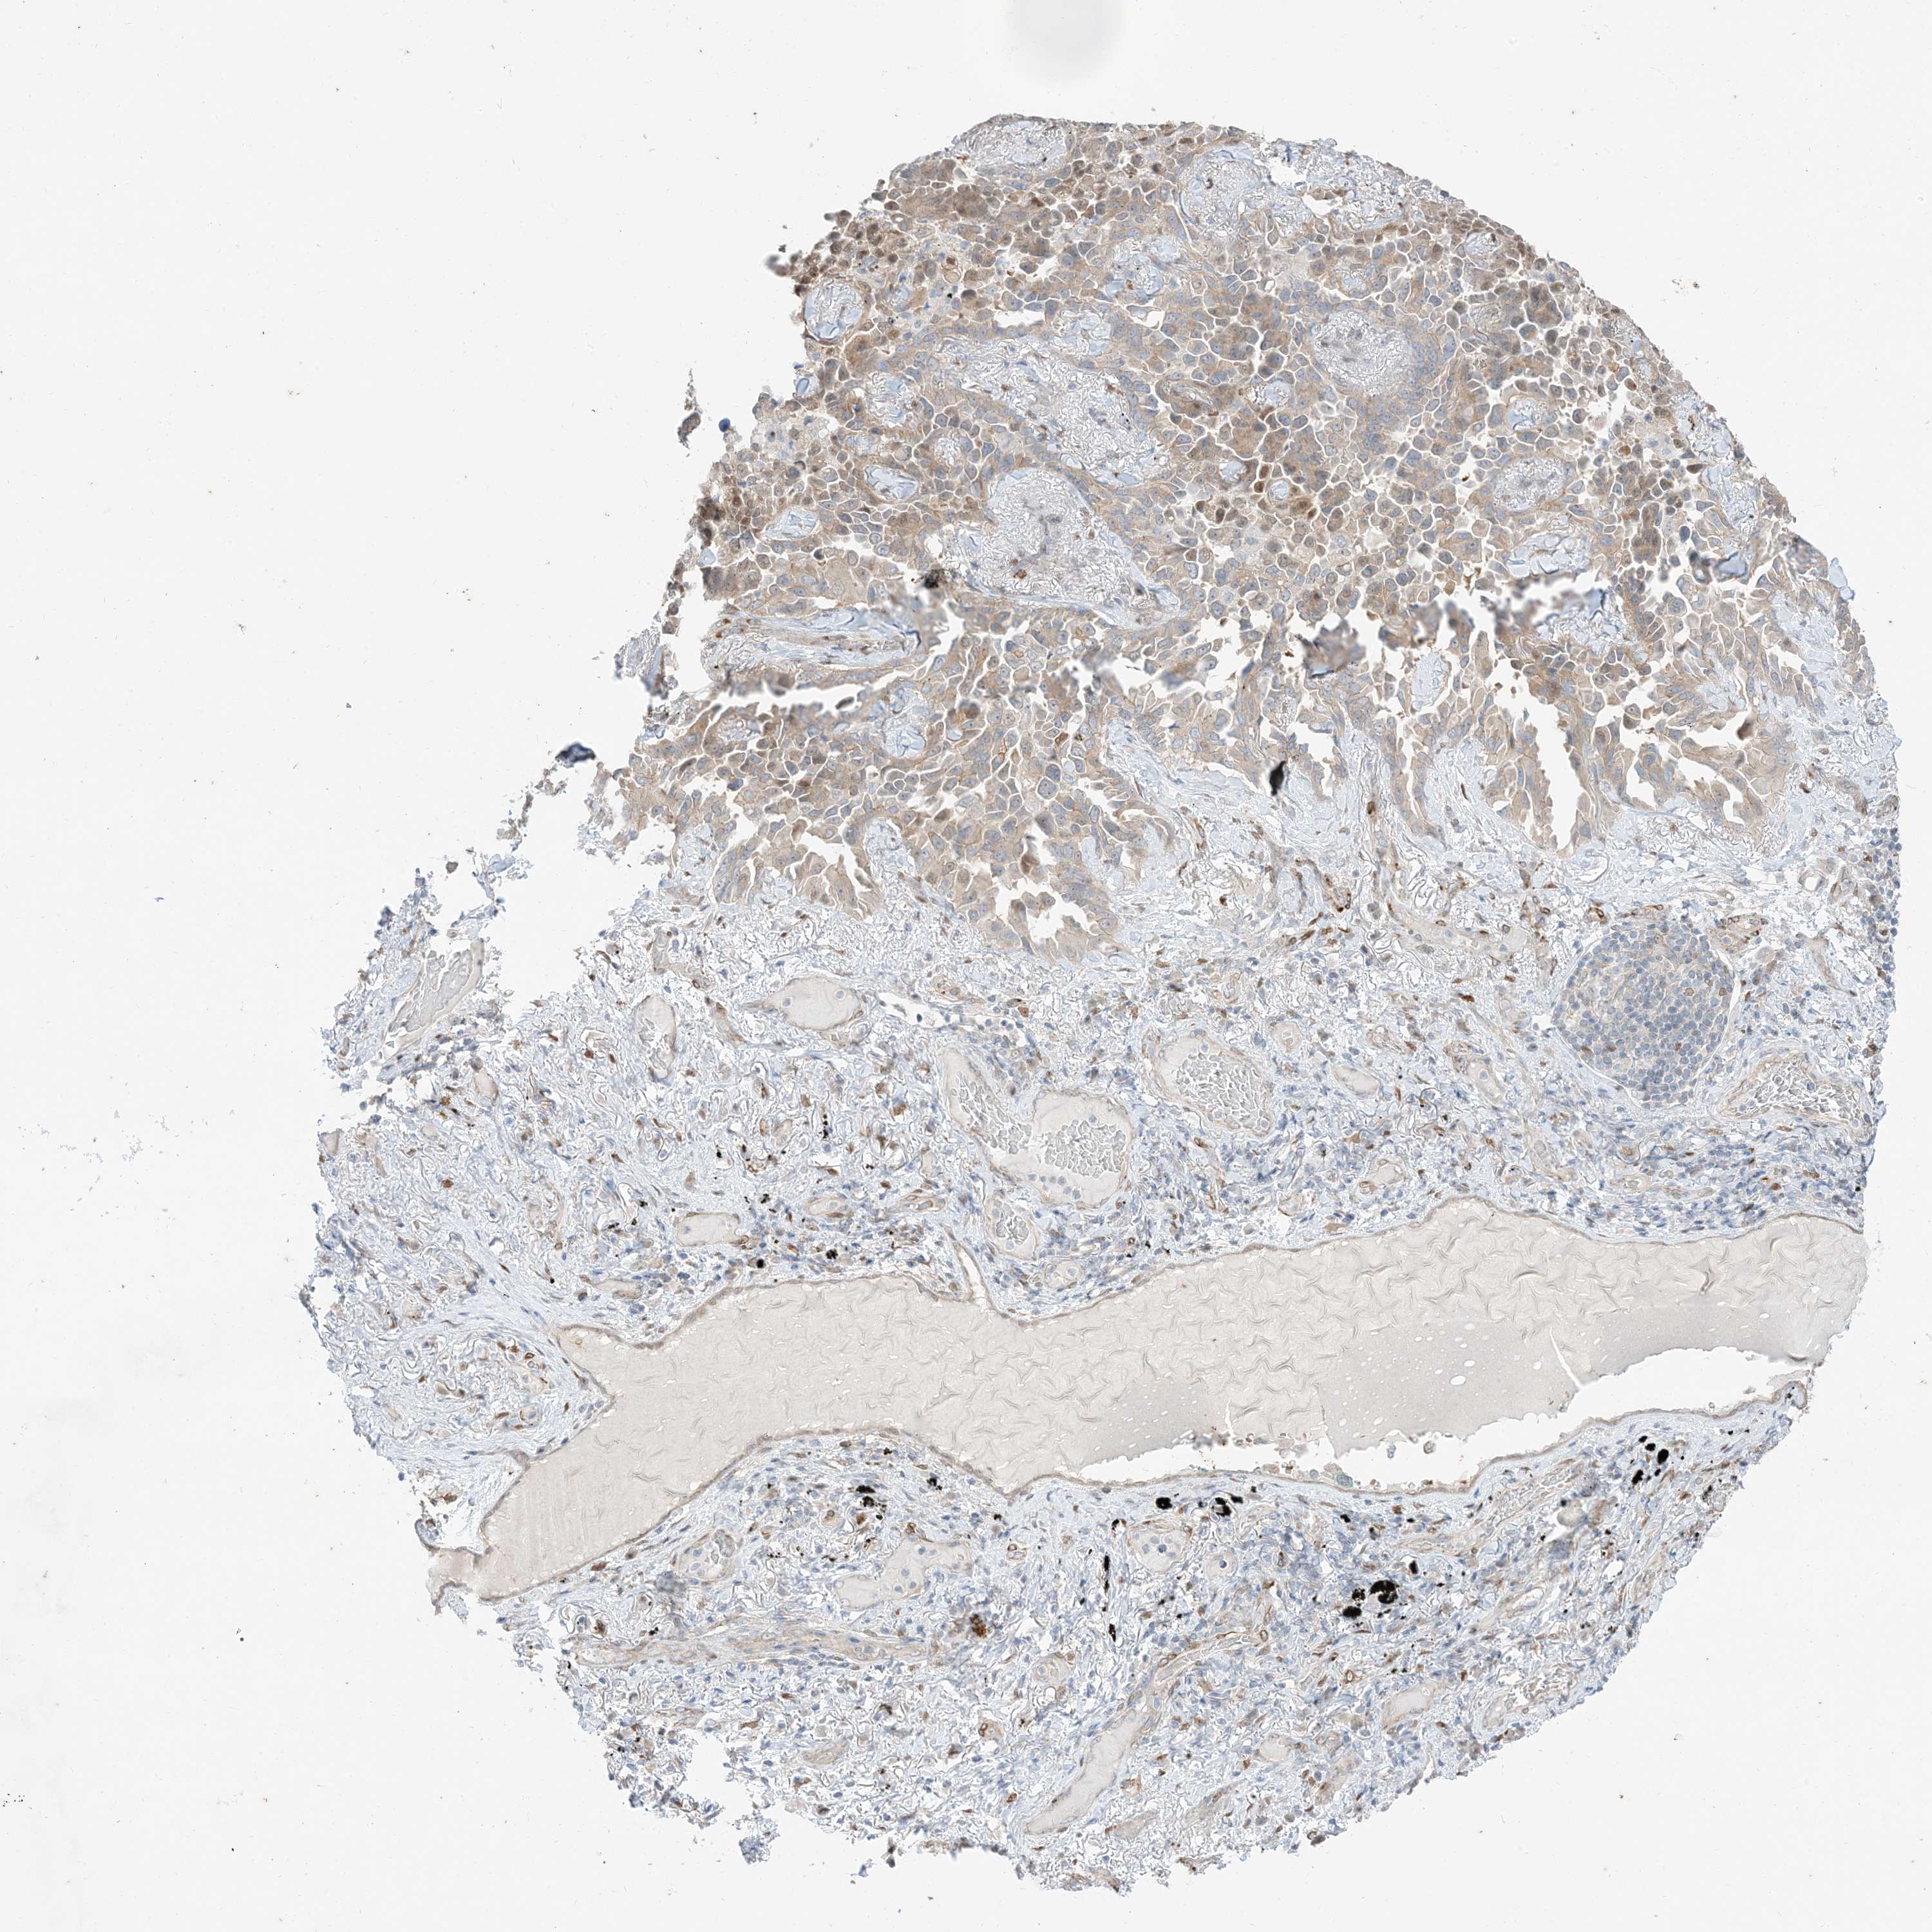

LUNG ADENOCARCINOMA (VALIDATION) - Interactive survival scatter ploti

The Survival Scatter plot shows the clinical status (i.e. dead or alive) for all individuals in the patient cohort, based on the same data that underlies the corresponding Kaplan-Meier plots. Patients that are alive at last time for follow-up are shown in blue and patients who have died during the study are shown in red.

The x-axis shows the expression levels (FPKM) of the investigated gene in the tumor tissue at the time of diagnosis. The y-axis shows the follow-up time after diagnosis (years). Both axes are complimented with kernel density curves demonstrating the data density over the axes. The top density plot shows the expression levels (FPKM) distribution among dead (red) and alive patients (blue). The right density plot shows the data density of the survived years of dead patients with high and low expression levels respectively, stratified using the cutoff indicated by the vertical dashed line through the Survival Scatter plot. This cutoff is automatically defined based on the FPKM cutoff that minimizes the p-score. The cutoff can be changed by dragging the vertical line or by entering a cutoff value in the square labeled "Current cut-off".

Under the Survival Scatter plot the p-score landscape (black curve; left axis) is shown together with dead median separation (red curve; right axis). Dead median separation is the difference in median mRNA expression between patients who have died with high and low expression, respectively. It is calculated as follows: median FPKM expression of dead patients with high expression - median FPKM expression of dead patients with low expression. This is intended to aid the user in visually exploring custom cutoffs and the associated p-scores and dead median separation.

Individual patient data is displayed and can be filtered by clicking on one or more of the category buttons on the top of the page. Categories describing expression level and patient information include: high, low, alive, dead, female, male and tumor stages. The scale of the x-axis can be toggled between linear and log-scale by clicking on the "x log" button. Mouse-over function shows TCGA ID, patient information and mRNA expression (FPKM) for each patient.

& Survival analysisi

Kaplan-Meier plots summarize results from analysis of correlation between mRNA expression level and patient survival. Patients were divided based on level of expression into one of the two groups "low" (under cut off) or "high" (over cut off). X-axis shows time for survival (years) and y-axis shows the probability of survival, where 1.0 corresponds to 100 percent.

RIN1 is not prognostic in Lung Adenocarcinoma (validation)

Best expression cut offi

Based on the FPKM value of each gene, patients were classified into two groups and association between prognosis (survival) and gene expression (FPKM) was examined. The best expression cut-off refers the FPKM value that yields maximal difference with regard to survival between the two groups at the lowest log-rank P-value. Best expression cut-off was selected based on survival analysis .

When clicking on this number, the vertical dashed line indicating cut-off, the interactive survival plot, and the Kaplan-Meier curve will be adjusted to show results based on the best expression cut-off.

: 1.38

P scorei

Log-rank P value for Kaplan-Meier plot showing results from analysis of correlation between mRNA expression level and patient survival.

N/A

TCGA RNA samplesi

RNA-seq data is reported as average FPKM (number Fragments Per Kilobase of exon per Million reads), generated by the The Cancer Genome Atlas (TCGA) .

Normal distribution across the dataset is visualized with box plots, shown as median and 25th and 75th percentiles. Points are displayed as outliers if they are above or below 1.5 times the interquartile range. FPKM values of the individual samples are presented next to the box plot.

Average pTPM 1.0

Number of samples 105